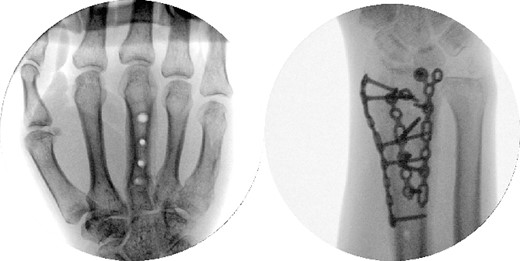

Two weeks following the procedure, the patient returned to the clinic for a follow-up visit. The wrist was swollen and ROM was limited. Hand motor functions and neurovascular exam were fully intact. Radiographs taken in clinic showed intact hardware with healing fracture. At 2 months follow-up, radiographs showed intact hardware with interval bone bridging across fracture sites. Radiographic parameters including articular alignment, radial height, radial inclination, and volar tilt were in acceptable ranges (Fig. 5). The patient reported no concerns or complications. A computed tomography (CT) scan was obtained at 10 weeks after the procedure and confirmed adequate bony healing and alignment without failure (Fig. 6). The dorsal spanning plate was eventually removed 1 month later and 4 months since the initial operation (Fig. 7).

Dorsal spanning plate hardware removal at 4 months with a PA view.

The patient followed-up in clinic 1 week after hardware removal. Clinically, the patient had no complaints. ROM was limited with both flexion/extension and supination/pronation. A QuickDASH assessment was obtained with a score of 25 out of 100, equating to minimal functional disability overall. Specifically, the patient reported moderate difficulty with washing his back and manual labor, and severe difficulty with impact recreational activities. The patient was to return to clinic in 4–6 weeks after undergoing physical therapy /occupational therapy to reassess ROM and functionality; unfortunately, the patient was lost to follow-up.